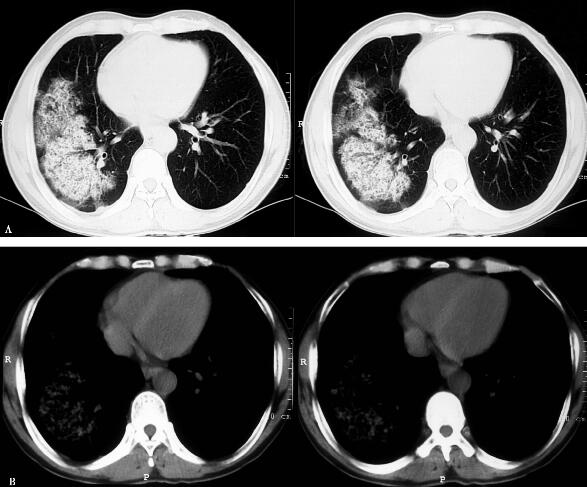

5.胸部影像学:

右肺大片斑片影(图1 A肺窗,B纵隔窗)。

图1

胸部影像学示右肺大片斑片影;血常规示中性粒细胞百分比增高,CRP、PCT明显增高、尿常规示高倍镜下白细胞、红细胞都明显增高。结合患者的病史和体格检查结果,进一步支持感染性疾病——社区获得性肺炎、泌尿系感染的诊断。考虑红细胞及尿蛋白异常与泌尿系感染有关,进一步完善痰培养、尿培养等相关病原微生物学检查,患者目前肾功能异常,考虑患者存在重症感染,累及肾脏所致。

患者为中年男性,慢性咳嗽、咳痰及间断咯血,近1周发热,无鼻窦炎的病史,无双手指间关节的疼痛,无口腔溃疡,无口眼干涩等风湿系统疾病的临床表现,既往无粉尘接触史,无其他肺部疾病史。胸部查体时的右肺下湿啰音为细小水泡音,更接近于帛裂音。辅助检查:胸部CT示双肺斑片影,且短期内迅速进展,血常规示小细胞低色素贫血,尿常规示高倍镜下红细胞、尿蛋白持续偏高,肾功能进行性恶化,血气示氧分压进行性下降。

结合上述资料,考虑患者为肺出血-肾炎综合征或ANCA相关血管炎的可能性大,胸部影像学改变考虑为肺出血-肾炎综合征或ANCA相关血管炎的肺部表现。进一步完善:①抗核抗体系列、ANCA明确是否有ANCA相关血管炎等相关风湿免疫系统疾病;②抗肾小球基底膜抗体测定,明确是否有肺出血-肾炎综合征;③完善鼻窦CT及四肢肌电图明确是否有鼻部及肌肉神经传导受累(ANCA相关血管炎易累及鼻部及肌肉神经);④肾穿刺行肾活检组织检查,病理能明确肾脏受累的具体病因。结果:抗肾小球基底膜抗体阳性,肾穿刺示肾小球囊上皮可见新月体形成,证实了肺出血-肾炎综合征的诊断。